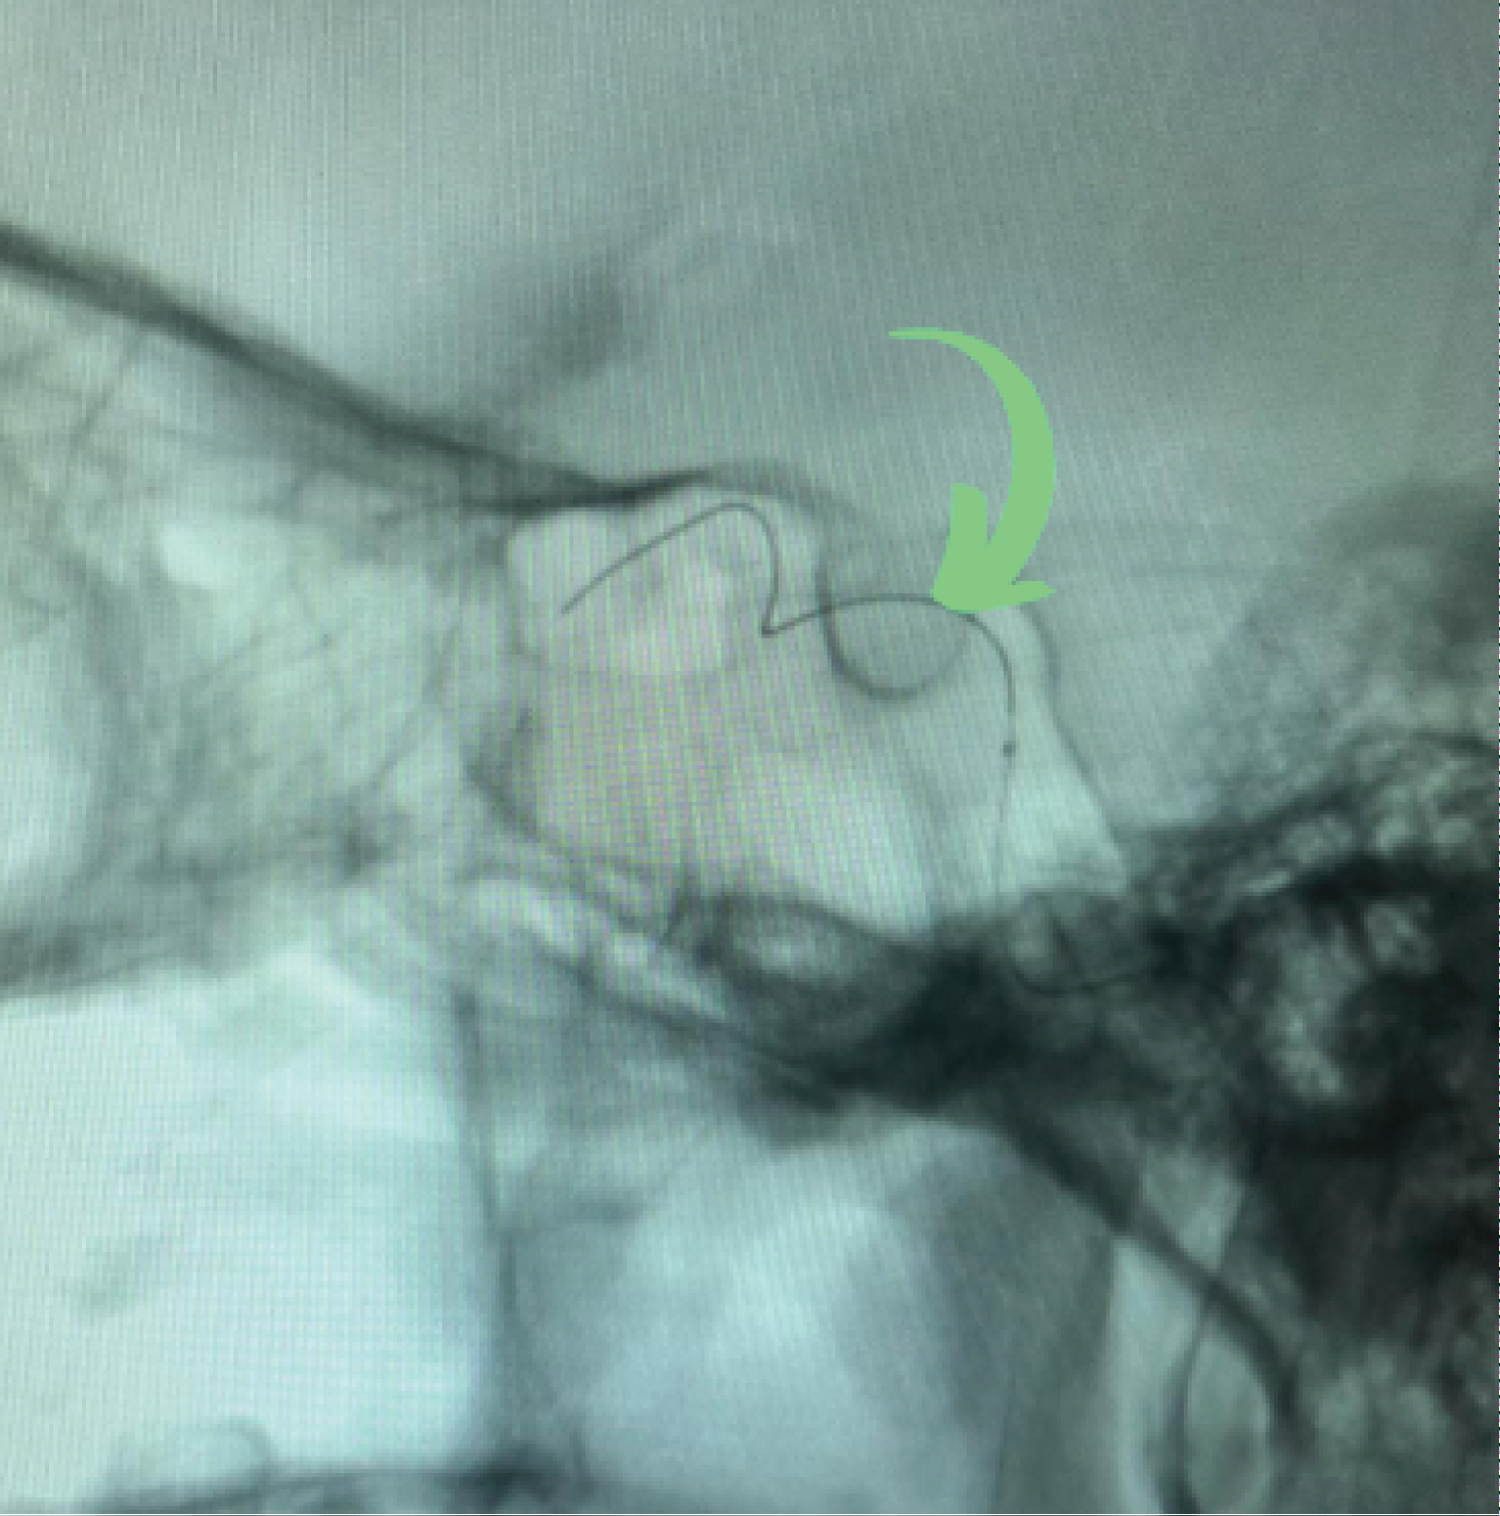

Positioned the 6F introducer sheath in the right femoral artery using the technique described by Seldinger; systemic heparinization performed with 5,000 IU of venous heparin. Positioned the 6F guide catheter in the left carotid artery with the aid of a hydrophilic guide wire of 0.035-150 cm; in angiography series, a large partially thrombosed aneurysm in the left internal carotid artery in the cavernous segment with a fistulous component was documented (Figure 3), along with dilation of the ophthalmic veins. Microcatheterization of the C5 segment of the ICA was performed assisted by a 0.14 micro-guide wire, reaching the superior ophthalmic vein through the cavernous sinus (Figure 4). Ten coils were then placed, with a satisfactory angiographic result (Figure 5). At the time of hospital discharge, clinical improvement was already reported, and at the 30-day follow-up appointment, the patient was asymptomatic. In the third month, during the outpatient follow-up, symptom recurrence was observed, and on the control angiography, fistula recurrence with coil migration within the cavernous sinus was evident (Figure 6). This case report was documented with the patient's signature on the informed consent form.

Figure 4: Angiography of the left internal carotid artery (LICA) arterial phase in profile (PE) demonstrating microcatheter in the superior ophthalmic vein (green arrow). View Figure 4